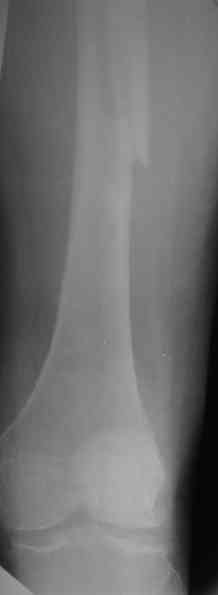

1. Представляющей наибольшую ценность из представленной информации следует считать фасные снимки №3и №4 (если считать по порядку). На снимке №3 не видны ни проксимальный отдел бедра с зоной (линией) перелома - наложение тени, ни дистальная зона (линия) перелома - область не захвачена. Снимок №4 демонстрирует дистальную линию перелома, но не показывает уровень конца ножки эндопротеза. В таких сучаях как способ можно выполнять снимок "с метками" - чтобы при при наложении снимков на негатоскопе иметь целостностное представление о всём сегменте от тазобедренного до коленного суставов.

2. Не совсем так. Перелом В2 (по C. Duncan и B.A.Masri, 1995) - перелом на уровне ножки эндопротеза или непосредственно дистальнее её конца с нестабильностью ножки, но хорошим качеством кости проксимального отдела бедра. Как известно, по статистике - наиболее часто встречающийся тип перипротезного перелома при первичном эндопротезировании. Очевидно - продольное раскалывание проксимального фрагмента в данном случае вызовёт нестабильность ножки.

А максимальная изогнутая LCP - 18 дырок, 336 мм.

прямая- 24 дырки 440 мм.

Снимок №4 демонстрирует дистальную линию перелома, но не показывает уровень конца ножки эндопротеза.

Кончик ножки виден на самом верху этого снимка.